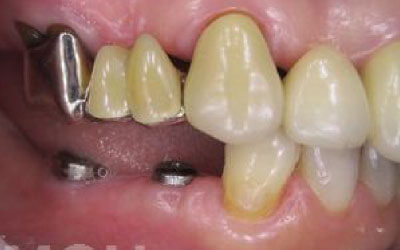

特に、抜けたのが前歯ですとなおさら気になりますよね。 今回のご質問ですが、抜けた部分の骨が薄いなどの理由で「インプラントはできない」と言われた可能性があります。

前歯はもともと骨が薄く、歯が抜けると時間の経過とともにさらに骨が痩せてきてしまうので、インプラント治療の難易度が高い場所です。 ただ結論からお話すると、インプラント治療は可能です。

なぜなら、もし仮に骨が薄くても、骨の治療によって厚みが増せば、安全にインプラント治療が行えるからです。

なお、前歯のインプラント治療をご希望の方には、注意していただきたい点が4つほどあります。 1)インプラント治療を行う前に、骨の治療が必要かもしれません。

2)骨の治療から始めると、その分、治療期間が長くなります。

3)骨の治療は、通常のインプラント治療よりも難易度が高いため、経験の豊富な先生やインプラント認定医のいる歯科医院で治療を受けることをお勧めします。

4)骨の状況をしっかり把握するためにも、CT撮影が必須となります。 また、インプラント治療においては、周囲の歯の状況や咬み合わせの問題などもしっかりと考えて治療するのがとても大切です。

そのため、残っている歯についてもきちんと診査してくれるクリニックが良いでしょう。 インプラント治療には、「インプラントを入れたら終了」というイメージがありますが、治療後、どれだけ長くインプラントがもつのかが最も大切なことなので、しっかりとメンテナンスしてもらえる歯科医院を選んでください。 まずは、いくつかの歯科医院でインプラントの相談をして比較検討し、ご自身が良いと感じた先生のところで治療を受けることをお勧めいたします。